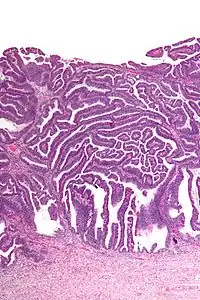

| Micrograph of a villoglandular adenocarcinoma the cervix. H&E stain. | |

The name of the lesion describes it microscopic appearance. It has nipple-like structures with fibrovascular cores (papillae) that are long in relation to their width (villus-like), which are covered with a glandular pseudostratified columnar epithelium.

Very low magnification